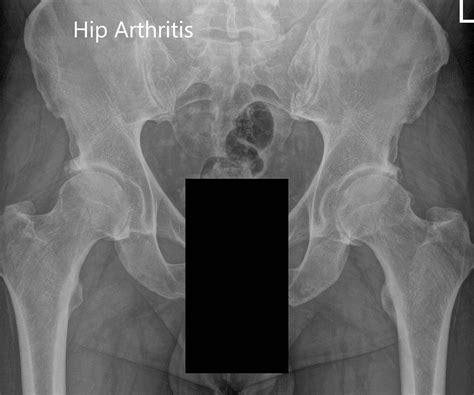

Marie Alderman Blog